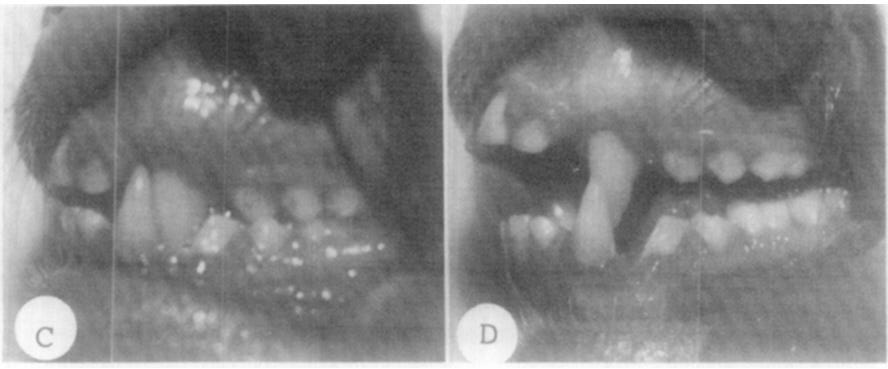

1981年美國加州舊金山California大學顱面畸形中心,哈佛醫師為了研究口呼吸對人類的影響,研究者針對一群恆河幼猴進行鼻腔呼吸(對照組) vs 口腔呼吸(實驗組)的實驗。在這項實驗的動物中,口腔呼吸是透過用矽膠鼻塞阻塞鼻道而發展起來的。實驗過程中發現,這群猴子以不同的方式適應鼻塞。有些保持著張開的嘴、有些有節奏地增加了口腔通氣,而另一些下巴位置往下掉(無論舌頭是否突出)。 六個月後,實驗組的猴子逐漸獲得與對照組不同的面部外觀和咬合改變,牙弓變窄、牙齒歪斜、咬合不正之外,下巴更因爲外旋內縮,使側臉鬆垮變長。

結束實驗後,雖然部分猴子回到了原本的鼻呼吸,但也有一部份伴隨著成年後固定為口呼吸(所以實驗還是有點殘忍呀!)。但由這個實驗結果我們可以知道,錯誤的口呼吸方式不只會改變臉型,也會使原本正常的口腔功能改變、咬合不正,不只使鼻呼吸越來越荒廢之外,還會加劇口呼吸的惡性循環。